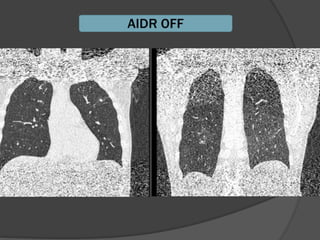

Ventana en TCARVentana en TCAR

 «El grosor de la pared bronquial en TCAR deberá«El grosor de la pared bronquial en TCAR deberá

estudiarse, con un nivel de ventana entre -250 yestudiarse, con un nivel de ventana entre -250 y

-700 UH y una amplitud de ventana mayor de-700 UH y una amplitud de ventana mayor de

1,000 UH.1,000 UH.

 Con una amplitud de ventana inferior a 1,000 UHCon una amplitud de ventana inferior a 1,000 UH

se producirá un engrosamiento artificial de lase producirá un engrosamiento artificial de la

pared bronquial.pared bronquial.

Ortega M y col. Utilidad de la radiografía de tórax yOrtega M y col. Utilidad de la radiografía de tórax y

de la tomografía computada de alta resolución»de la tomografía computada de alta resolución»

Alergia , asma e inmunologia pediatricaAlergia , asma e inmunologia pediatrica

Vol20,num3 sep-dic 2011Vol20,num3 sep-dic 2011